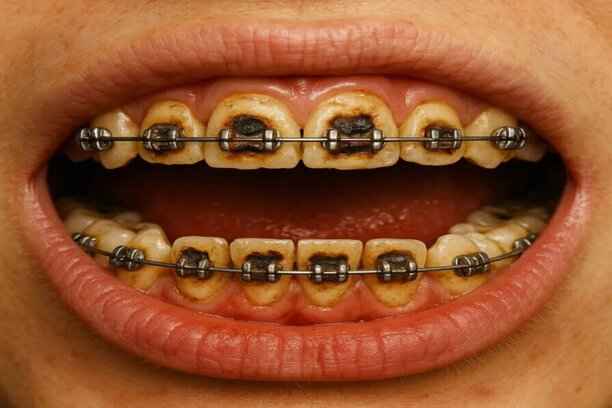

مشاكل شائعة لتقويم الأسنان

رغم فعاليته، قد تصاحب التقويم بعض التحديات المؤقتة، وهي غالبًا قابلة للإدارة. أشهر المشاكل تشمل:

- الشعور بالألم أو الضغط في الأيام الأولى.

- تقرحات بسيطة في الخد أو الشفاه.

- صعوبة مؤقتة في المضغ أو النطق.

- تراكم بقايا الطعام حول الأجهزة.

- فك أو كسر أحد مكونات التقويم.

- حساسية الأسنان عند تناول المأكولات الباردة.

المتابعة المستمرة في مركز أضواء الحكمة تضمن التعامل السريع مع هذه المشكلات دون التأثير على مسار العلاج.

أضرار تقويم الأسنان

رغم فوائده الكبيرة، قد تظهر بعض الآثار المؤقتة إذا لم يُدار العلاج بشكل صحيح. من الأضرار المحتملة:

- ألم مؤقت في بداية العلاج.

- تهيج خفيف في اللثة أو الخد.

- صعوبة مؤقتة في المضغ.

- تآكل مينا الأسنان عند إهمال النظافة.

في مركز أضواء الحكمة، تُدار هذه التحديات بوعي وخبرة، لتبقى فوائد تقويم الاسنان لكبار السن أكبر بكثير من أي آثار جانبية محتملة.